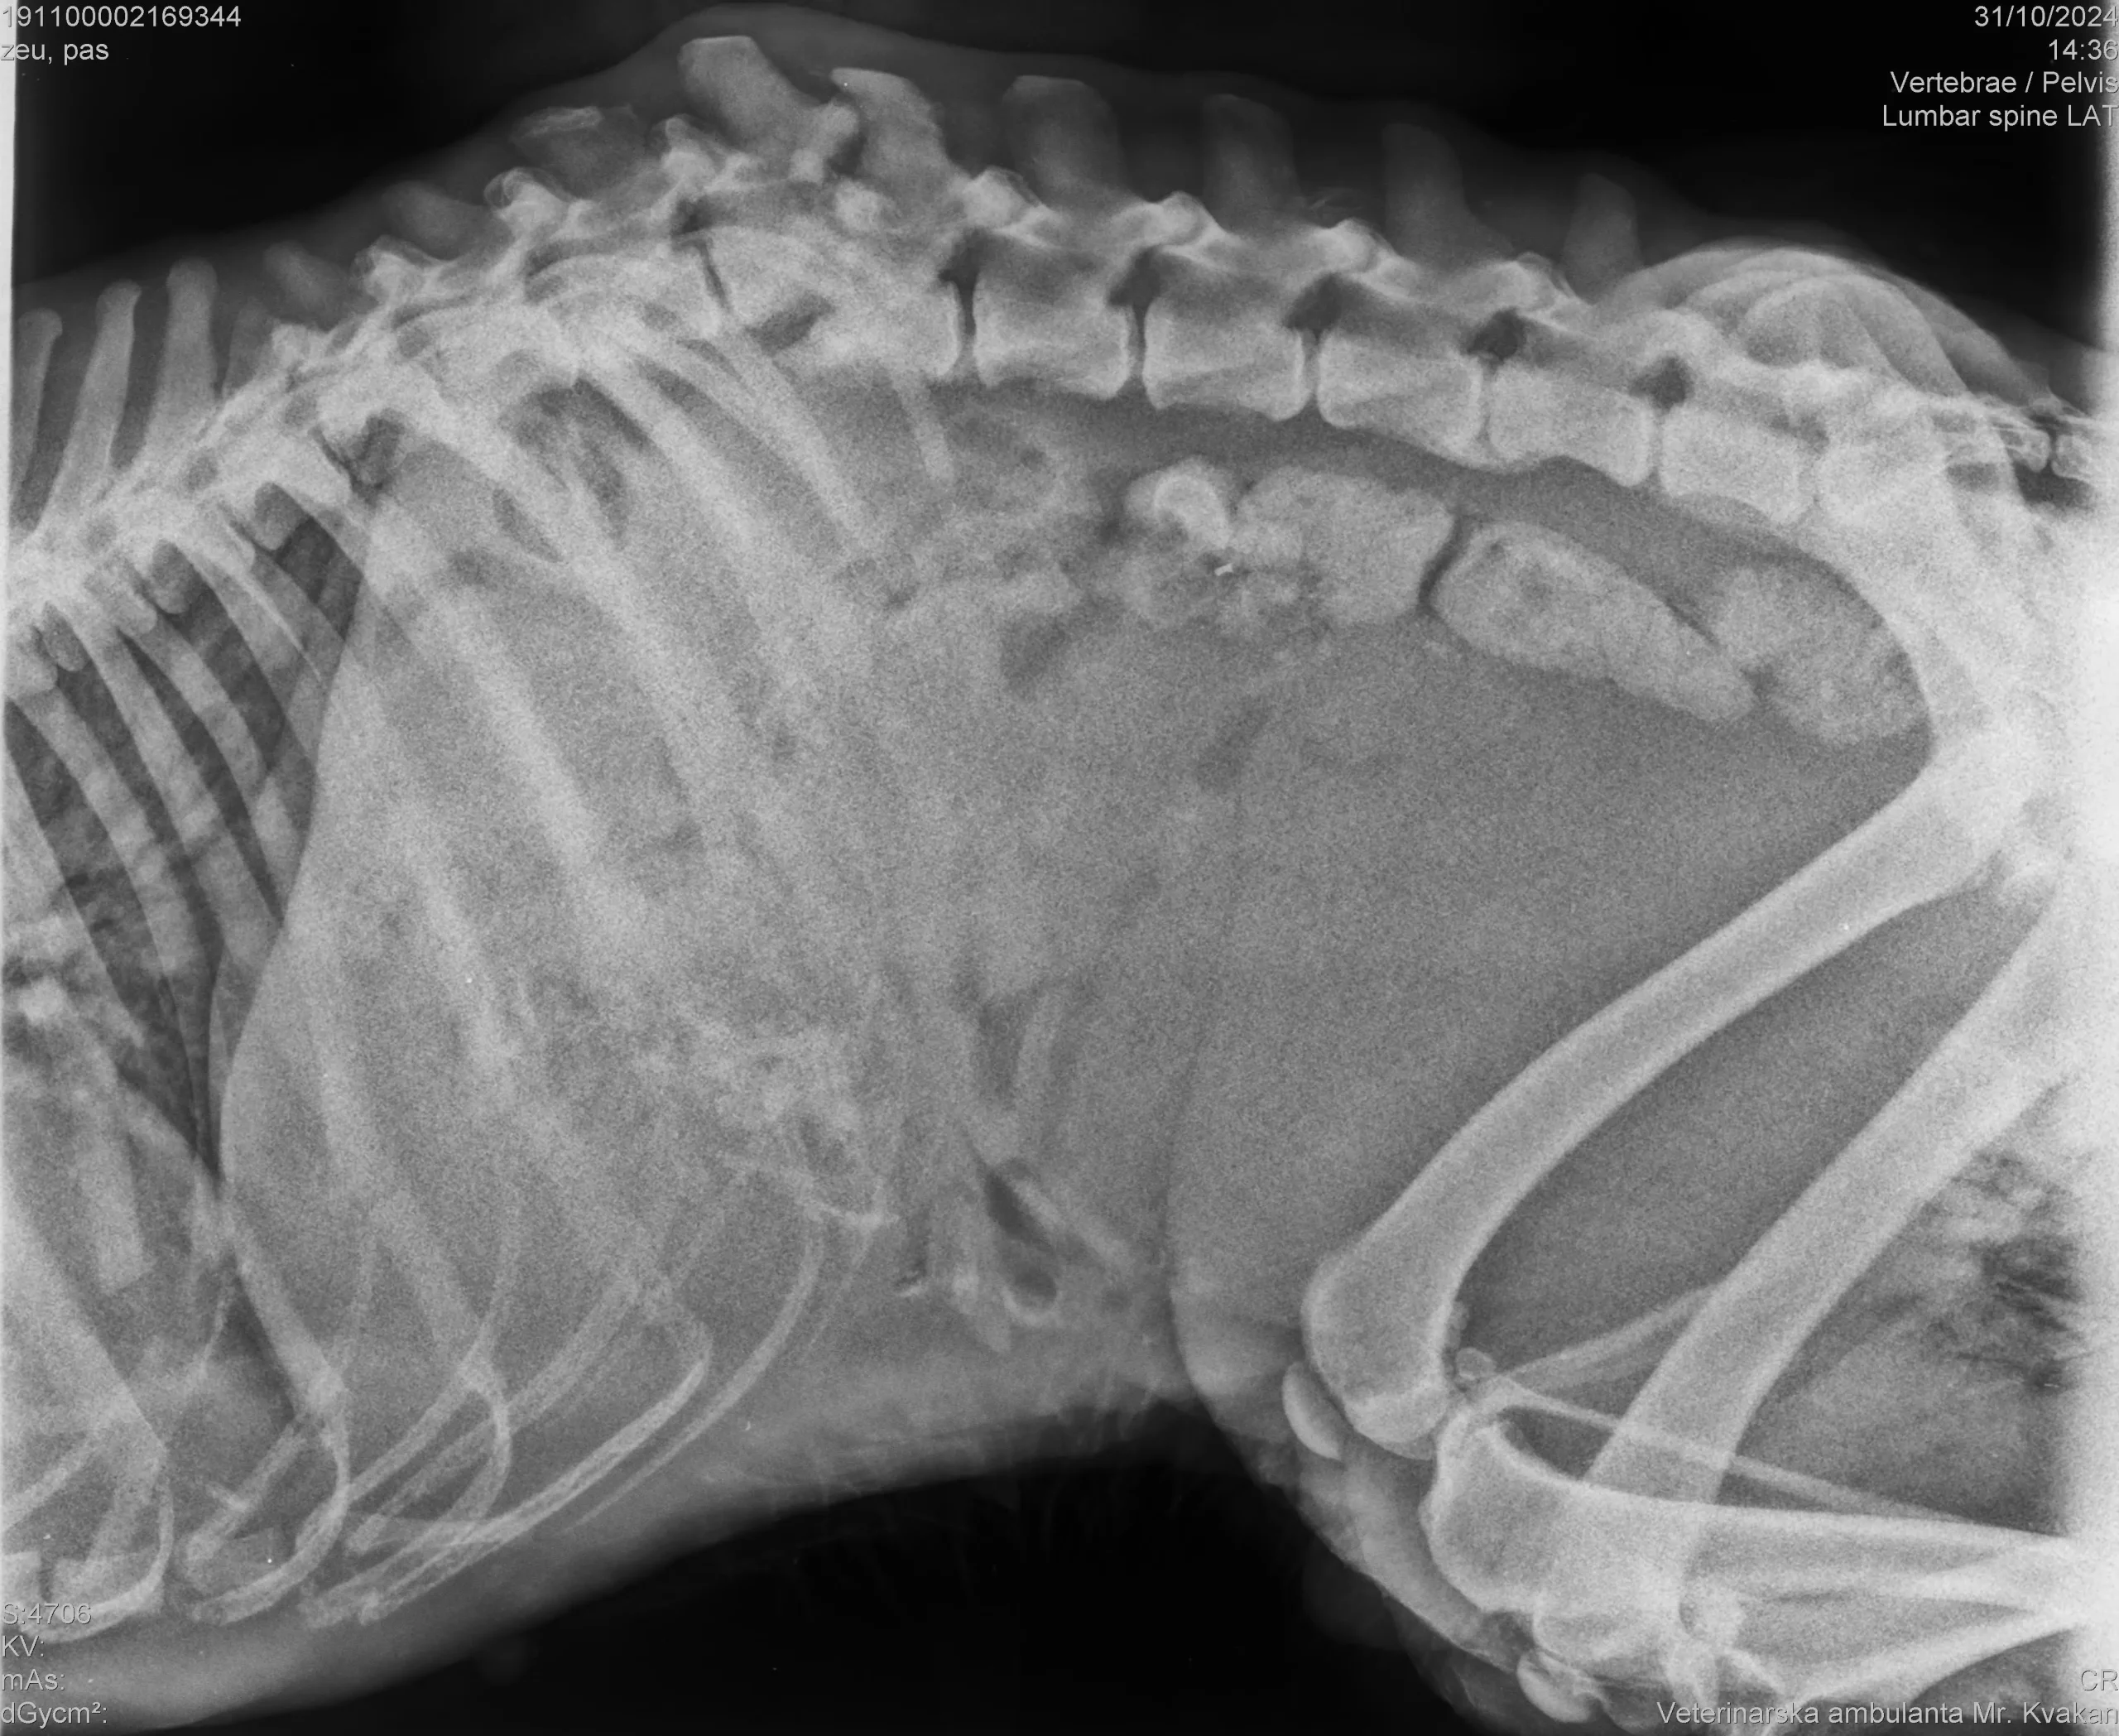

Danas su ga do skloništa dovezli stanovnici naselja Pribislavec nakon što se u teškim bolovima i teško povrijeđen (slomljene kralježnice i odrezane noge) vukao po ulici.

Zbog teških ozljeda, pas je eutanaziran. Kaznena prijava bit će podnesena DORH-u.